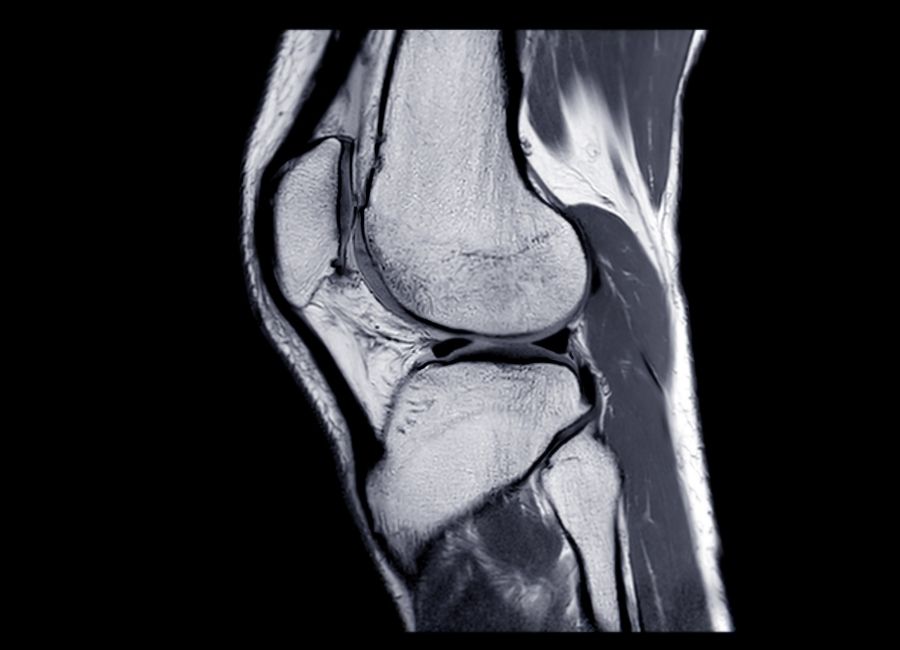

Menisküs yırtığı

Diz eklemi, vücudun en karmaşık ve en çok kullanılan eklemlerinden biridir. Hareket sırasında yükün büyük bir kısmını taşıyan bu eklemde menisküs adı verilen kıkırdak yapılar yer alır. Menisküsler, diz eklemini korur, yük dağılımını sağlar ve hareketin sorunsuz gerçekleşmesine yardımcı olur. Ancak ani hareketler, spor yaralanmaları ya da yaşlanmaya bağlı olarak bu kıkırdak yapılar zarar görebilir. Ortaya çıkan menisküs yırtığı kişide ciddi ağrıya, dizde takılma hissine ve hareket kısıtlılığına neden olur. Daha fazla bilgi için menisküs yırtığı üzerine uzman kaynaklara başvurulabilir.

Menisküs yırtıkları genellikle sporcularda sık görülür. Futbol, basketbol veya tenis gibi ani dönüşlerin yapıldığı sporlarda diz büyük bir baskıya maruz kalır. Bunun dışında günlük hayatta da ani çömelme veya ağır yük kaldırma sırasında menisküs hasar görebilir. Özellikle 40 yaş üzerindeki kişilerde menisküs dokusunun zayıflaması, daha küçük hareketlerde bile yırtık oluşmasına sebep olabilir.